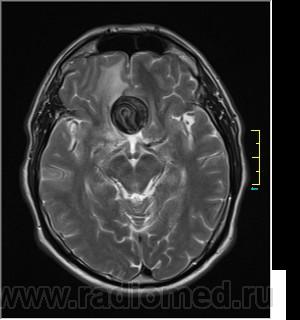

Ax T2:

частично функционирующая аневризма

Иначе говоря, аневризма с хронической геморрагией, т.к. мы видим фракции крови различного возраста.

По-моему, аневризма с пристеночными тромбами.

Постепенное пристеночное образование тромбов приводит к появлению типичного для аневризмы феномена -слоистости МР сигнала в полости аневризмы. Данная картина демонстрирует слоистый характер тромботических масс в полости аневризмы .Функционрирующая часть имеет низкий сигнал во всех режимах сканирования. Дополнительно-перифокальный отек.

А может более корректно интерпретировать как частично тромбированная аневризма... Уж коь речь идет о фракциях, ну то есть о тромбе по сути.... Ну и плюс перфокальный отек головного мозга (вероятнее цитотоксический+вазогенный).